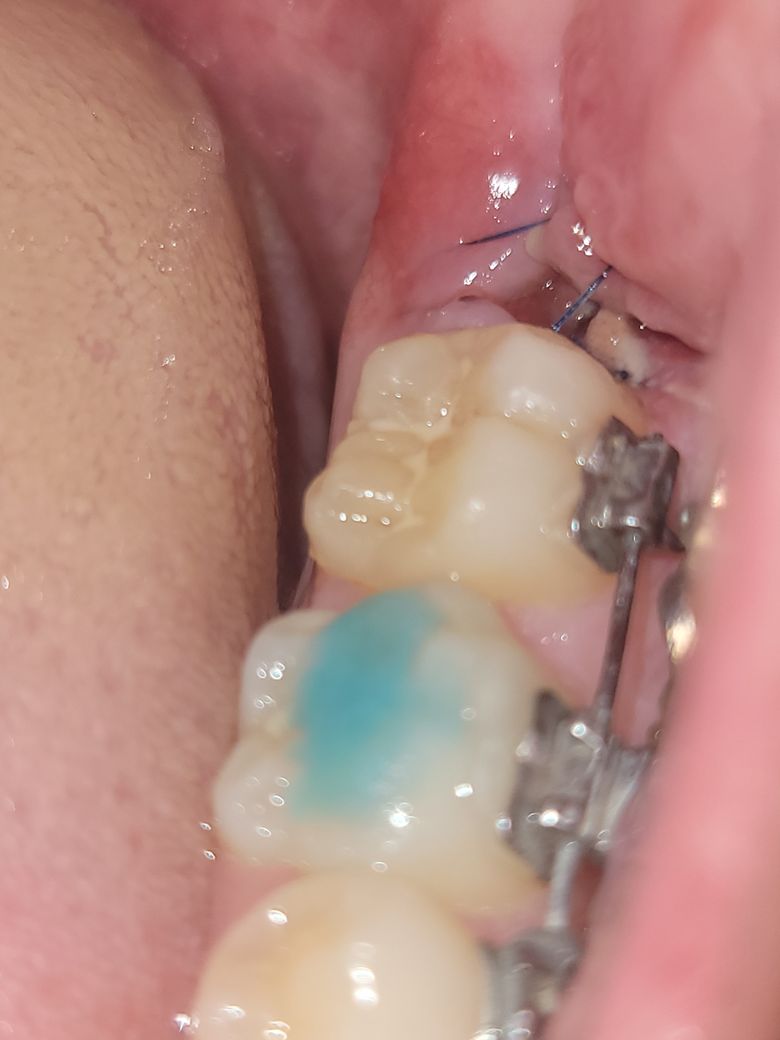

사랑니 발치 후 5일차인데 잘 아무는 중인가요?

사랑니 발치 하고 5일됐는데 잘 아무는 중인지 궁금합니다.

그리고 흰색 덩어리가 음식물인 것같은데 가글로 안빠져서 어떻게 빼는게 나을지 알려주시면 감사하겠습니다

염증 등의 이상 소견이 보이지는 않습니다 . 이물질의 경우에는 제거를 해보고 안되면 그대로 두셔도 됩니다.

사진상으로 보면 발치한곳은 잘 아물고 잇는거 같습니다. 음식을 드시고 나서 물로 여러번 헹궈주시면될것같습니다.

잘 아무는 것으로 보입니다. 일단 가글로 빼내는 수밖에 없습니다.

안 빠진다고해서 뾰족한 도구로 무리하게 빼내지는 마세요.

사진으로 볼 때 발치한 부위는 잘 아물고 있는 것으로 보입니다. 내부에 이물질이 길 수 있지만 억지로 제거하지 않는 것이 좋습니다. 억지로 제거하다 상처가 나게 되면 출혈이 되고 치유가 늦어질 수 있기 때문입니다.

현재 사진상 잘아물고 있는 것으로 보이며, 발치 부위에서 흰색 덩어리가 나타날 수 있는데, 이는 음식물이 아니고 섬유지족일 가능성이 높습니다. 발치 부위에서 자연스럽게 형성되는 이 덩어리는 조직이 아물어 가는 과정에서 나타날 수 있으며, 억지로 제거하지 말고, 소독용 헥사메딘 가글액으로 가글하여 염증이 덧나지 않게 관리를 하여주길 권합니다.